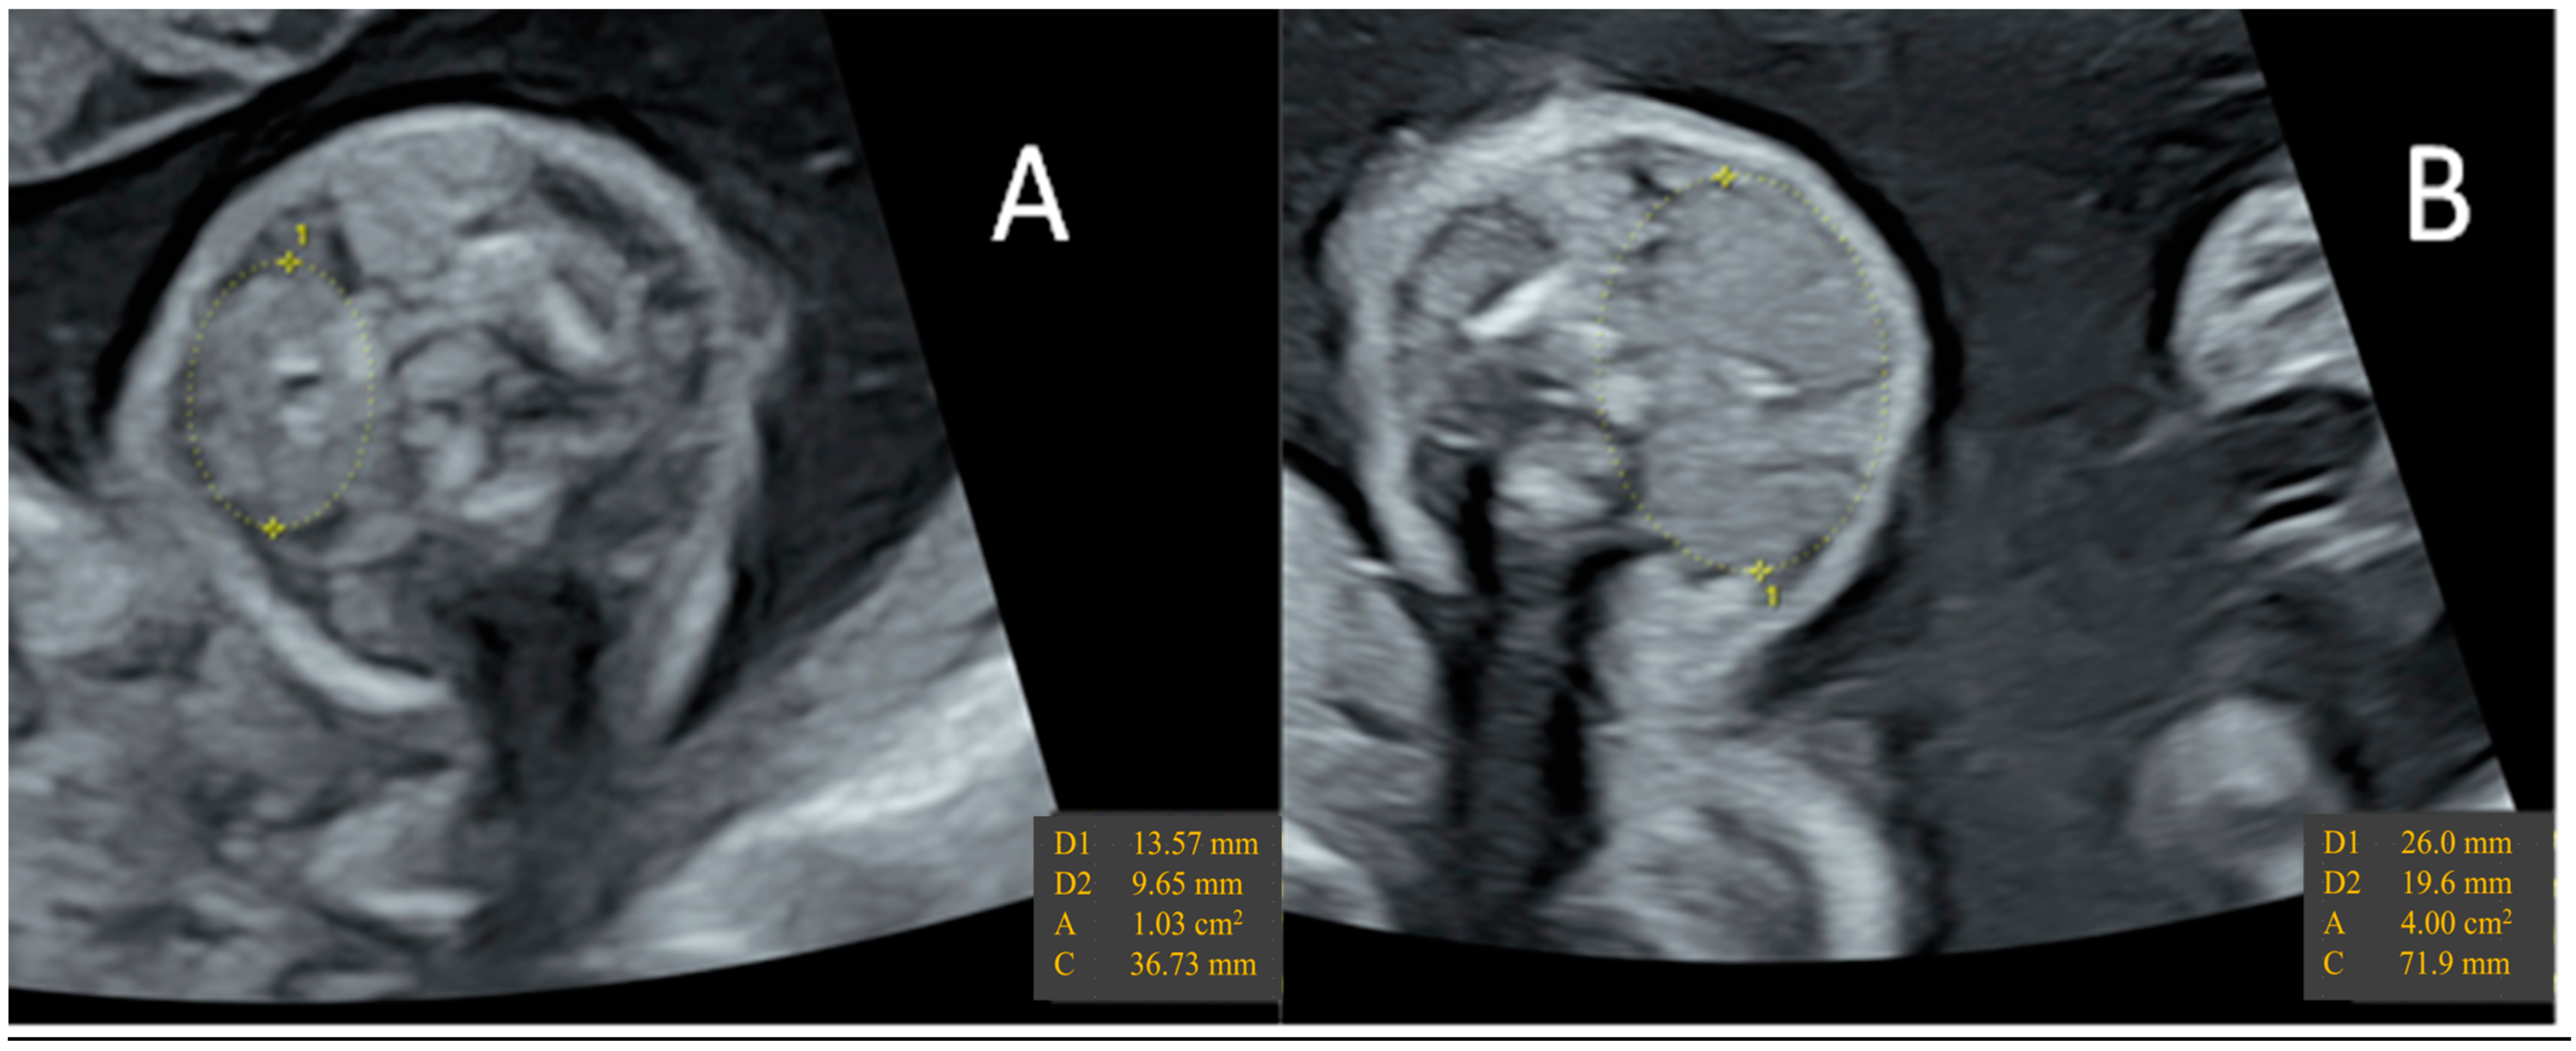

- Huel, C.; Guibourdenche, J.; Vuillard, E.; Ouahba, J.; Piketty, M.; Oury, J.F.; Luton, D. Use of ultrasound to distinguish between fetal hyperthyroidism and hypothyroidism on discovery of a goiter. Ultrasound Obstet. Gynecol. 2009, 33, 412–420. [Google Scholar] [CrossRef]

- Ranzini, A.C.; Ananth, C.V.; Smulian, J.C.; Kung, M.; Limbachia, A.; Vintzileos, A.M. Ultrasonography of the fetal thyroid: Nomograms based on biparietal diameter and gestational age. J. Ultrasound Med. 2001, 20, 613–617. [Google Scholar] [CrossRef]